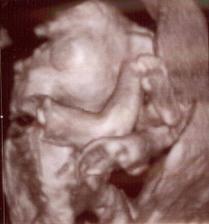

Toto je ten najkrajší zázrak na svete 🙂)) Dňa 10.6. 2009 potvrdená akcia srdiečka nášho bubáčika a rastieme ako z vody - máme 12,6 mm. Už teraz sa tešíme na prvú poradňu ktorá bude 1.7. na ktorej nám dajú vytúženú tehu knižočku a obrázok nášho zázraku 🙂)) Dňa 20.9. sme boli na 3D ultrazvuku, kde nám pán doktor povedal, že čakáme chlapčeka 🙂)) Tak sa z neho veľmi tešíme 🙂))